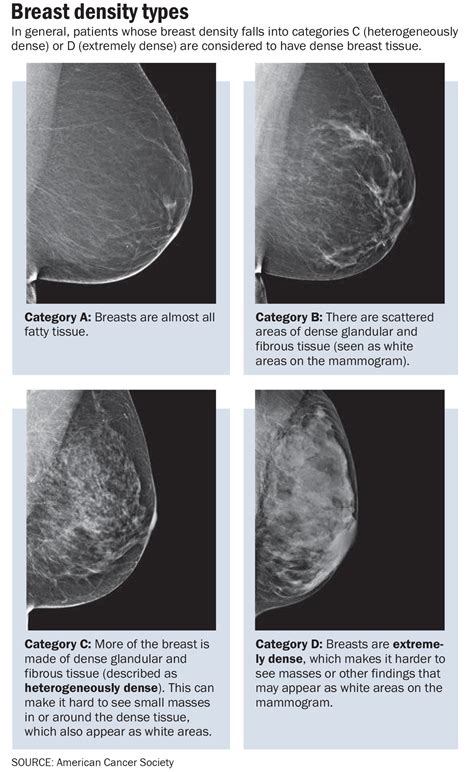

Normal mammogram images can vary depending on the individual's breast tissue density. Breast tissue density is categorized into four types:

Category Description

Almost entirely fatty The breasts are mostly composed of fatty tissue, making it easier to detect abnormalities.

Scattered areas of fibroglandular density The breasts have some dense tissue and some fatty tissue, which can make detection slightly more challenging.

Heterogeneously dense The breasts have a significant amount of dense tissue, which can obscure small abnormalities.

Extremely dense The breasts are almost entirely composed of dense tissue, making it the most difficult to detect abnormalities.

• Breast Tissue Density: Dense breast tissue can make it more difficult to detect abnormalities on a mammogram.

• Breast Tissue Density: Dense breast tissue can obscure small abnormalities, making them more difficult to detect.